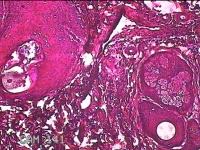

头部肿物

性别

男

年龄

18岁

临床诊断

头部局部肿物

一般病史

发现头顶部外凸结节半年余,近日出现局部破溃。

标本名称

大体所见

灰白暗红色肿物1.5x0.8x0.3cm一个,表面糜烂,结节表面有少许毛发,切开结节呈实性,切面灰白粉红色,质软。